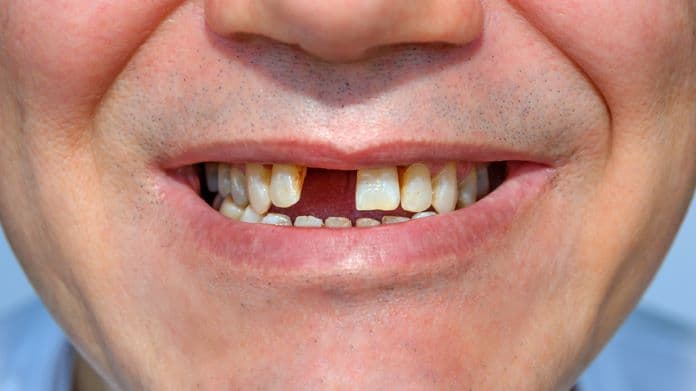

常見的缺牙原因,包括來自各種碰撞意外、牙齒蛀蝕以及牙周病等。近日研究報告證實,以牙齒缺失為例,缺牙可以增患認知障礙症的風險,原因是咀嚼運動受阻會影響腦部血流。正常情況下,人體於咀嚼運動後,大腦動脈的血液流速度會明顯提高,相應腦區的供血量亦增加,而長期缺牙(尤其牙齒缺失數量較多而致咀嚼運動受影響者),則可令咀嚼功能紊亂。

研究還指出,相比牙齒數目健全的受檢者,缺牙者的大腦血流速度明顯減慢,腦供血量也明顯減少,這亦會促使相應的神經組織結構和功能衰退及產生變化,足以干擾側額葉、海馬體、顳葉皮質及基底核腦的血流速度、血容量等,以及大腦神經介質的分泌量,影響大腦的正常機能運作,因而促使認知功能問題的發生。